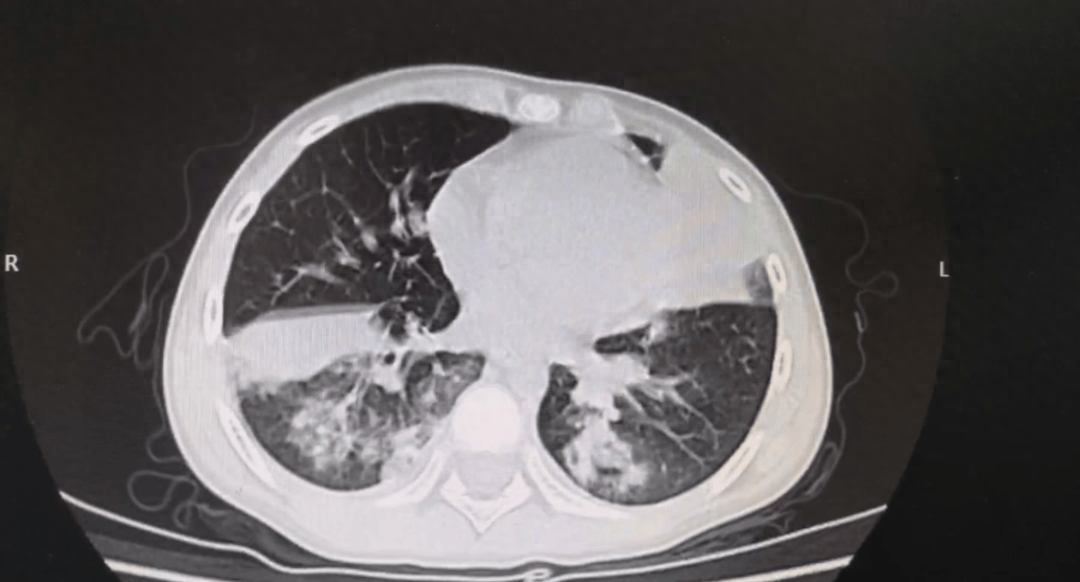

目前,支原体肺炎的诊断主要依靠支原体抗体检查和血清冷凝集试验以及鼻咽拭子的核酸检测。影像学表现是临床判断病情严重程度和评估预后的主要依据之一,肺炎支原体肺炎早期胸片或胸部CT主要表现为支气管血管周围纹理增粗、增多、支气管壁增厚,可有磨玻璃影、“树芽征”、小叶间隔增厚、网格影等,再结合上述检测即可作出诊断。

下面展示的是一组重症肺炎患儿经气管镜灌洗的前后变化,不难看出,灌洗后的肺部炎症,较之前明显吸收。

气管镜灌洗前

气管镜灌洗后